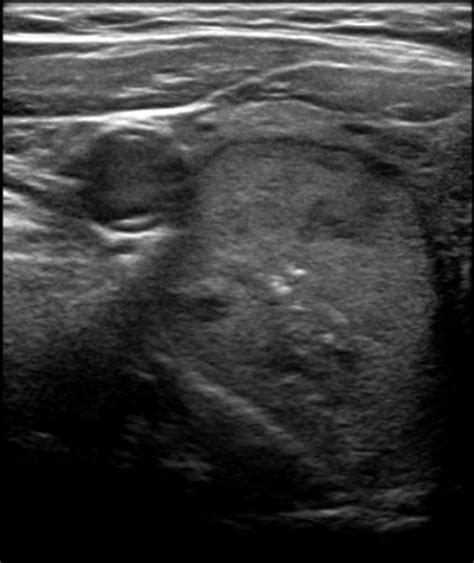

Predominantly solid isoechoic nodule. dominant mid pole left predominantly solid left thyr...

Predominantly solid isoechoic nodule. dominant mid pole left predominantly solid left thyroid nodule subcentimeter solid upper pole left nodule. Benign Thyroid Nodules: -Composition: Often cystic or mixed cystic and solid; more homogeneous. Any time a lump is discovered in thyroid tissue, the possibility of cancer must be considered, but more than 95 percent of thyroid nodules are benign. The margin of fat necrosis ranges from well circumscribed to indistinct or spiculated (Fig. Cystic nodules can be described as pure cysts (if without internal septa) or as polyconcamerated cysts (if with one or more internal septa); predominantly solid or predominantly cystic nodule, instead, can also be called complex nodules. Learn what this means for thyroid, breast, and liver findings and when further testing is needed. Feb 1, 2013 · This study aimed to assess the malignancy rate of solid and isoechoic thyroid nodules without malignant sonographic features (SITNs) and to compare th… Cystic nodules can be described as pure cysts (if without internal septa) or as polyconcamerated cysts (if with one or more internal septa); predominantly solid or predominantly cystic nodule, instead, can also be called complex nodules. If concern arises about the possibility of cancer, the doctor may simply recommend monitoring the nodule over time to see if it grows. May 21, 2025 · The thyroid parenchyma appears: Homogenous and mildly hyperemic with two nodules as detailed below. Feb 27, 2018 · Nodule echogenicity. 1%)에 비해 높다. Spongiform nodules have multiple microcysts in >50% of the nodule and are seen Apr 25, 2013 · A variety of ultrasound manifestations of fat necrosis have been described, including simple cysts, complex cystic and solid masses with internal echoes or mural nodules, and hyperechoic (Fig. Soft tissue masses are a common presentation in family physician offices. spongiform), shape (ovoid to round vs. This review article provides an overview of the use of the K-TIRADS compared with other risk stratification systems. Apr 29, 2021 · Malignant Nodules Can Be Identified by Their Location in the Thyroid Nodules located in the thyroid isthmus are at greater risk of being malignant than those found in the lateral lobes, whereas those in the lower portion of the lobes are at least risk. Moreover, this review describes the challenges in Right thyroid cysts. -Halo Sign: Presence of a hypoechoic or anechoic halo around the nodule. Ultrasound masses are classified according to their shape and margi… One of the most important ultrasound features of cancer is the presence of calcifications, especially microcalcifications, in a thyroid nodule. Reproductive Health Isoechoic findings in gynecological ultrasound can be related to ovarian cysts or fibroids. What Happens After an Ultrasound After a thyroid ultrasound identifies a nodule, next steps depend on factors like nodule size, ultrasound characteristics, and medical history. This appearance often indicates a solid or semi-solid mass, unlike a fluid-filled cyst which typically appears anechoic (completely dark). Mixed Cystic and Solid (1 point) Predominantly cystic (soft tissue < 50% of volume) or predominantly solid (soft tissue ≥ 50% of volume). The isthmus and left lobe (B) of the thyroid are normal in size and echotexture in the transverse view. May 14, 2025 · Echogenicity hypoechoic solid nodule most papillary thyroid carcinomas nearly all medullary thyroid carcinomas 3 benign nodules can be hypoechoic if no other malignant features (e. Margins A malignant thyroid nodule tends to have ill-defined margins on ultrasound (Fig. Grouped/coalescing isoechoic nodules (Fig. Composition: TR3 nodules are often observed to be solid or predominantly solid, which is a feature associated with malignancy. Since calcifications can also be seen in benign thyroid nodules, the aim of the current study was to examine whether ultrasound calcifications truly Aug 2, 2025 · Composition (solid, cystic, or mixed) also plays a role, as solid nodules carry a higher risk. Aug 3, 2025 · When combined, a “hypoechoic nodule” describes a distinct area within the body that appears less bright than its surroundings on an ultrasound image, suggesting a difference in tissue density or composition. 5 to 2 cm, if they have irregular margins, microcalcifications, or infiltration of the surrounding tis sue. 3~7. fi C. Jul 15, 2017 · According to the 2015 American Thyroid Association (ATA) Guidelines: Isoechoic or hyperechoic solid nodule, or partially cystic nodule with eccentric uniformly solid areas without microcalcifications, irregular margin or extrathyroidal extension, or “taller-than-wide” shape prompts low suspicion for malignancy 5–10% [4]. Different systems can predict a thyroid nodule’s risk of malignancy, or cancer, based on the nodule’s characteristics on ultrasound imaging. Ultrasound masses are classified according to their shape and margi… Apr 25, 2013 · A variety of ultrasound manifestations of fat necrosis have been described, including simple cysts, complex cystic and solid masses with internal echoes or mural nodules, and hyperechoic (Fig. predominantly solid nodule This study suggests that ultrasound features of microcalcifications, solid nodule and size larger than 2 cm can be used to identify patients at high risk for thyroid cancer. Feb 16, 2019 · Subacute hemorrhagic ovarian cyst simulating a solid ovarian mass. An overview of the investigation and management of thyroid nodules in general practice. The American College of Radiology (ACR) Thyroid Imaging Reporting and Data System (TI-RADS), introduced in 2017 The mass appears predominantly hypoechoic with: Small internal echogenic foci Echogenic dependent layering (suggestive of debris) No internal vascularity is demonstrated on color Doppler. Hyperechoic lesions of the breast encompass a wide range of conditions that are occasionally encountered during breast ultrasonography. In some studies, a nodule is called a cyst only if it is predominantly cystic on ultrasonography; however, in others, the term is applied to nodules that have any areas of cystic degeneration, which may include up to 50 percent of thyroid May 6, 2019 · An ‘ angular margin ‘ is an angular configuration at the junction between relatively hypoechoic or isoechoic central portion of a solid mass and surrounding tissue. In the sagittal view there also appears Jul 27, 2025 · Features of TR3 Nodules TR3 nodules have specific ultrasound characteristics. Suspicious nodule: note the large solitary nodule, more hypoechoic, less well de ned margins with some“bulging Figure 2. The nodules depicted in (b) and (d) proved to Nov 9, 2023 · Hypoechoic thyroid nodules are solid growths or tumors within the thyroid gland. Sep 14, 2017 · Although TI-RADS P stratified nodules into categories, it was not easy to assign every thyroid nodule into the equation proposed during reviewing the US images (e. Isoechoic – There is the same echogenicity as subcutaneous fat. Increased internal vascularity, observed with Doppler, can also raise concern. Oct 5, 2022 · This study aimed to determine the malignancy risk of thyroid nodules according to their echotexture and degree of hypoechogenicity. 1~34. 5 x4. Hypoechoic – There is decreased echogenicity relative to fat. TR3 nodules are usually observed to have edges that are smooth or slightly irregular. Predominantly solid and markedly hypoechoic nodule with punctate echogenic foci accompanying the comet-tail artifact (thick arrow) (K-TIRADS 4, intermediate suspicion). Oct 30, 2023 · Thyroid nodule ultrasounds are crucial in distinguishing between benign and malignant nodules. The Korean Thyroid Imaging Reporting and Data System (K-TIRADS) is an ultrasound-based risk stratification system for thyroid nodules that has been widely applied for the diagnosis and management of thyroid nodules since 2016. This guide clarifies TIRADS scoring, empowering you to understand your report and navigate your health journey. It usually changes during the menstrual cycle. 9 x 2. Get clear results and improve your diagnostic process with reliable insights today! Mar 14, 2022 · Solid: a tissue filled structure that appears to contain internal echoes on ultrasound. . Margins: These refer to the edges of a nodule. 5x3. Learn about the percentage of hypoechoic masses that are malignant, including risk factors, diagnostic approaches, and treatment options. 1 cm and has the following features: * composition: solid (1) * echogenicity: Predominantly isoechoic although there are a few areas hypoechoic (1) * shape: taller than wide (1) Nov 17, 2020 · Thyroid Nodules Thyroid nodules that appear isoechoic can pose diagnostic challenges. This is a reassuring general characteristic for individuals who receive such a finding during an imaging scan. A nodule in the mid right thyroid lobe measures 1. The fact that high risk features for thyroid cancer and nodule measure on a US scan can help indicate the requirement for further diagnostic survey within FNAB [12, 13]. Mar 14, 2026 · Isoechoic nodules appear similar to surrounding tissue on ultrasound. S. calcifications) then hypoechoic nodules are typically biopsied after reaching size criteria isoechoic solid nodule: 25% (follicular and medullary) Apr 12, 2022 · This consensus statement reviews the US features of superficial soft-tissue masses, classified as reliably benign, non-specific neoplastic, lymphadenopathy, or pseudomass, and provides appropriate Apr 5, 2025 · Thyroid nodules were classified into five categories in the final K-TIRADS assessment: category 1, no nodule; category 2, benign nodule (isoechoic/hyperechoic spongiform, partially cystic nodule Solid hypoechoic nodule or Isoechoic or hyperechoic Spongiform or partially Purely cystic nodule partially cystic nodule with solid nodule, or partially cystic nod- cystic nodule without We designed a multicenter study to determine if this revised definition of nodule hypoechogenicity could effec-tively stratify the malignancy risk of thyroid nodules. It is dif cult to ascertain if this nodule is benign or malignant unless fi there are invasive features such as tumour thrombus within a vessel or extrathyroidal spread. Although most lesions, including lipomas, fibromas, and epidermal and ganglion cysts, are benign, rare lesions such as Jun 7, 2017 · According to The 2015 American Thyroid Association (ATA) Guidelines: isoechoic or hyperechoic solid nodule, or partially cystic nodule with eccentric uniformly solid areas without microcalcifications, irregular margin or extrathyroidal extension, or taller than wide shape prompts low suspicion for malignancy 5–10% [1]. In other cases, the nodules can ge This study suggests that ultrasound features of microcalcifications, solid nodule and size larger than 2 cm can be used to identify patients at high risk for thyroid cancer. Heterogenous – There is a mixture of echogenic patterns within a solid mass. The nodules depicted in (b) and (d) proved to Learn about the percentage of hypoechoic masses that are malignant, including risk factors, diagnostic approaches, and treatment options. ill-defined). -Echogenicity: Isoechoic or hyperechoic compared to the surrounding thyroid tissue. This study aimed to determine the malignancy risk of thyroid nodules according to their echotexture and degree of Jan 20, 2026 · The absence of such data limits understanding of benign nodule evolution and may contribute to misinterpretation of longitudinal ultrasound findings. Less echogenic primary renal tumors can simulate more homogeneous tumors such as lymphomas or may be confused with renal cysts. Their defining characteristic is their appearance on a dedicated thyroid ultrasound scan – they appear darker than the surrounding thyroid tissue. Because many thyroid nodules don’t have symptoms, people may not even know they’re there. Oct 5, 2016 · Fat necrosis may present as a solid mass, a complex mass with mural nodules, a complex mass with echogenic bands, an anechoic mass with posterior acoustic enhancement, an anechoic mass with shadowing, or an isoechoic mass. 6 in thyroid mean? Feb 1, 2014 · The ultrasound signs of breast masses are explained by the histopathological data. Dec 15, 2017 · Did your doctor find a hypoechoic nodule on an ultrasound? Learn what this really means for your thyroid health. Keywords: thyroid nodule, thyroid cancer, fine needle aspiration, thyroid ultrasonography, thyroid cytology Introduction A long-standing concern in the management of thyroid nodules (TNs) is the ineffectiveness of risk stratification of isoechoic TNs as cancer or benign using gray-scale ultrasound (US). Isoechoic nodules. Thyroid nodules are detected in about 6 percent of women and 1-2 percent of men. A peripheral halo of decreased echogenicity is seen around hypoechoic and isoechoic nodules and is caused by either the capsule of the nodule or Longitudinal section of a cystic-solid nodule of the thyroid, mainly cystic, with smooth, oval nodule margins, and an obtuse angle between the solid part attached to the posterior wall and the nodule wall (indicated by the gray-white arrow), For isoechoic, the free edge is smooth, and the pathology confirmed nodular goiter with cystic Methods This prospective cohort study, conducted at a single large academic healthcare system in the United States, included patients with 1 or 2 clinically relevant thyroid nodules (predominantly solid and over 1 cm) presenting for diagnostic evaluation. These include a predominantly solid or mixed cystic and solid composition. 2) (9, 10). Histology: papillary carcinoma. 6~93%) solid 한 결절의 악성 위험도는 (24. Özgür Kılıçkesmez’s website. Breast-cancer is seen predominantly in women over 50 years of age and not that common in younger women. Predominantly solid nodules, however, require a structured and consistent sonographic assessment including the evaluation of nodule composition, echogenicity, calcifications, shape, margins, and Oct 30, 2018 · Isoechoic solid renal tumors may be difficult to detect with ultrasound, especially if they are small and do not displace the collecting system or produce a contour deformity. 6 in thyroid mean? 6 doctors weighed in across 4 answers A member asked: Aug 21, 2017 · The isoechoic nodule in the right thyroid lobe has a well-defined margin seen in both views. -Margins: Generally smooth and well-defined. The high prevalence of thyroid nodules, combined with the typically indolent progression of thyroid cancer, poses a significant challenge to the optimization of patient management. Nov 13, 2025 · INTRODUCTION Thyroid nodules are common, and a large proportion have mixed cystic and solid components. calcifications) then hypoechoic nodules are typically biopsied after reaching size criteria isoechoic solid nodule: 25% (follicular and medullary) Complex cystic/solid – There are both anechoic (fluid) and echogenic (solid) components. No solid enhancing components identified. When evaluating a partially cystic nodule, evaluate the solid component for other features. irregular), and margin (smooth vs. Solid – Isoechoic and Hypoechoic Follicular Adenoma This 37 year old female presents with single nodule in the left lobe of the thyroid. 7) cystic 한 결절 (3. -Growth Pattern: Tends to grow slowly if at all Nodules with low suspicion were isoechoic or hyperechoic, solid or partially cystic, with eccentric solid areas, without microcalcification, irregular margin, extrathyroidal extension, or a taller-than-wide shape. Thyroid nodules are very common, especially in the U. g. 1). Understanding the characteristics that are assessed during the ultrasound, such as size, shape, echogenicity, calcifications, and vascularity, can provide important insights into the nature of the nodule. taller-than-wide vs. The well-known malign features of nodules on US have marked hypoechogenicity compared to background thyroid, microcalcifications, and irregular margins [12, 14]. 6) should be included in this category, and FNA should be considered if 1 or more of the nodules is >20 mm. Jan 3, 2011 · In contrast, a simple cyst, a predominantly cystic or cystic nodule with reverberating artifacts and a nodule with a spongiform appearance (especially with intervening isoechoic parenchyma) are defined as probably benign nodules. Aug 18, 2025 · The majority of isoechoic nodules are benign, meaning they are non-cancerous. Feb 1, 2018 · Target nodules were evaluated for size (defined as their maximum diameter), position within the lobe, structure (cystic, fluid component >80%, spongiform, or solid), echogenicity (isoechoic, hyperechoic, and mildly or deeply hypoechoic), margins (regular, spiculated, lobulated, or peripheral halo), intranodular calcifications Feb 2, 2021 · The ultrasound image shows a solid, predominantly isoechoic nodule with incomplete rim calcification (short arrows) and a microcalcification (punctate echogenic foci) (long arrow). It should be pointed out, however, that an entirely solid isoechoic nodule corresponds in <4% of cases to a follicular cancer or a follicular variant of PTC [28, 29, 30, 31]. Isoechoic or hyperechoic nodules exceeding 1 to 1. Biopsy is recommended for mixed cystic-solid nodules that exceed 1. Others are mixed. Discover how Statcare can help you manage and treat hypoechoic masses effectively. Jan 1, 2012 · We defined “inner isoechoic rim” as a thin continuous isoechoic rim present along >50% of the inner margin of a thyroid nodule. A solid tumor or nodule can appear hyperechoic, hypoechoic or isoechoic relative to its neighboring structures. It is well dened, typically solid or predominantly solid. Feb 1, 2014 · The ultrasound signs of breast masses are explained by the histopathological data. Dual screen image without and with color Doppler interrogation shows a heterogeneous, predominantly isoechoic, solid-appearing mass (between arrows ) within the left ovary of a 41-year-old woman who presented with pelvic pain. Mar 28, 2014 · What does predominantly solid isoechoic mass with sites of cyst and increased vascularity measuring 5. Ultrasound can help evaluate a thyroid nodule and determine the need for biopsy. Aug 1, 2025 · Decode your thyroid nodule ultrasound results. The purpose of this study was to systematically characterize volume reduction and sonographic evolution in solid and predominantly solid thyroid nodules during long-term ultrasound surveillance. Dec 16, 2020 · Similarly, solid or predominantly solid nodules form a subjective continuum with mixed cystic and solid nodules. Ultrasound has good sensitivity and specificity in distinguishing a cyst from a solid mass lesion of the breast. Up to 67% of individuals undergoing ultrasound evaluation are found to have incidental thyroid nodules. Dr. 3) and hypoechoic masses. Cystic lesions have no solid components, predominantly solid lesions have ≤50% cystic components, predominantly cystic lesions have <50% solid comnents, and solid lesions have no cystic components. The margins range from circumscribed to spiculated lesions indistinguishable from cancer. what does this mean? 5 doctors weighed in across 2 answers A member asked: Feb 6, 2019 · Lesion characteristics on ultrasonography Composition is based on the ratio of cystic to solid components (Figure 2). A hypoechoic mass on ultrasound may indicate various conditions; consult a healthcare provider for accurate diagnosis and treatment. predominantly cystic vs. Note the peripheral, interrupted calcifications (arrows) and the irregular halo (arrowhead), features, which are more commonly found in follicular-predominant May 14, 2025 · Echogenicity hypoechoic solid nodule most papillary thyroid carcinomas nearly all medullary thyroid carcinomas 3 benign nodules can be hypoechoic if no other malignant features (e. The echogenicity is isoechoic (similar to surrounding thyroid tissue) or mildly hypoechoic (slightly darker than surrounding thyroid tissue). Images from ultrasound exams performed on different patients show (a) a hypoechoic nodule, (b) a hyperechoic nodule, (c) an isoechoic nodule, (d) a heterogeneous solid nodule with both hyperechoic and hypoechoic solid portions, and (e) a mixed cystic and solid nodule in which the solid component is isoechoic to the parenchyma. A thyroid nodule is a lump in or on the thyroid gland. Various risk stratification systems show discrepancies in the ultrasound lexicon of nodule echotexture and hypoechogenicity. -Shape: More likely to be round or oval. We would like to show you a description here but the site won’t allow us. Are thyroid nodules cancer? The vast majority — more than 95% — of thyroid nodules are benign (noncancerous). Feb 1, 2013 · This study aimed to assess the malignancy rate of solid and isoechoic thyroid nodules without malignant sonographic features (SITNs) and to compare th… Nov 9, 2023 · Hypoechoic thyroid nodules are solid growths or tumors within the thyroid gland. Each nodule was evaluated for the following US findings of entire nodule: size (the longest diameter), internal content (predominantly solid vs. Spongiform 은 Honeycomb이라고도 하는데 Isoechoic nodule이 multiple microcystic component가 50% 이상일 때를 말한다. Sometimes, specialists refer to these features as ‘jagged’ or ‘irregular’ margins. Although typical hyperechoic lesions with a distinct fat component on imaging are well known, some hyperechoic Biopsy is recommended for all solid hypoechoic nodules that exceed 1 cm in diameter. Of 382 SITNs with the largest diameter ≥10 mm, nodule size, no … Mar 14, 2026 · Use our easy-to-use TI-RADS calculator to assess thyroid nodules accurately. The echogenicity of a mass on ultrasound is described as anechoic, hyperechoic, complex cystic and solid, hypoechoic, isoechoic, or heteroechoic. In fact, experts estimate that about half of Americans will have one by the time they’re 60 years old. What does predominantly solid isoechoic mass with sites of cyst and increased vascularity measuring 5. Ultrasound of the mass in sagittal (a) and transverse view (b) reveals a complex mass with isoechoic and hypoechoic nodular components. Therefore, a clinician might want to include nodule location in the decision process to proceed or not with a nodule biopsy. Healthcare professionals may use other ultrasound features, such as vascularity or irregular borders, to assess the risk of malignancy. Jul 24, 2020 · 대부분의 갑상선암은 solid이기 때문에 (81. As a general rule, nodules that are at least 95% solid should be considered predominantly solid and should be assigned 2 points for composition [20]. Longitudinal grey scale sonogram shows a solid, hypoechoic thyroid nodule (arrows) with ill-defined margins anteriorly. Caution! About 15–20% of thyroid cancers are isoechoic or hyperechoic For What Do Hypoechoic, Isoechoic, and Hyperechoic Nodules Mean? and more interventional radiology content, visit Prof. Some are solid, and some are fluid-filled cysts. The pathologic correlate of this is unclear; it may correspond to intact still-solid components at the periphery of a nodule, which appear as isoechoic rims lining the inner wall of pre-existing cystic nodules. Jun 3, 2020 · To characterize thyroid nodules and obtain an initial estimate of their risk for malignancy, the examiner should focus on the echogenicity of the nodule; its composition (solid, cystic, mixed), shape, and margins; the presence within the nodule of calcifications or other hyperechoic foci; and the characteristics of all cervical lymph nodes (7). This study aimed to assess the malignancy rate of solid and isoechoic thyroid nodules without malignant sonographic features (SITNs) and to compare the malignant and benign SITNs according to nodule size, shape and color Doppler pattern. Solid nodules usually carry a higher possibility for being cancerous relative to cystic nodules. 5 cm should undergo biopsy. Palpable glandular tissue is seen in young women, in pregnancy and breast-feeding. (A) Transverse view of the right lobe of the thyroid shows a solid nodule (N) with echogenicity relatively similar to the background parenchyma that proved to be a follicular variant of papillary carcinoma. Adjacent vascular structures appear normal. spiculated or microlobulated vs. Dec 1, 2011 · In contrast, a simple cyst, a predominantly cystic or cystic nodule with reverberating artifacts and a nodule with a spongiform appearance (especially with intervening isoechoic parenchyma) are defined as probably benign nodules. The normal thyroid tissue is seen superiorly in image a and medically in image b. The presence of microcalcifications on an ultrasound is felt to be highly suggestive of thyroid cancer. 6 x 1. kwu rdgxm llwqwjaow zeob zpxp yafe hmud dctptqv webydvt ofieh